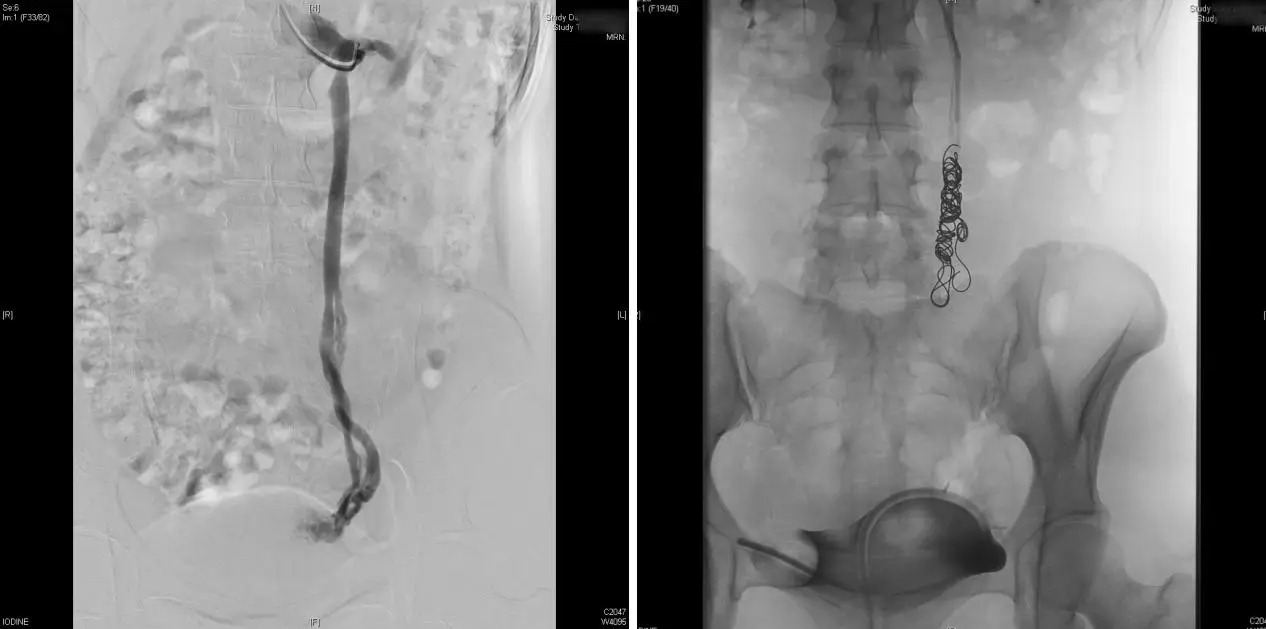

Hình ảnh sung huyết vùng chậu của chị Chen Fan

Sau khi tìm đúng "hang ổ" của bệnh, chị Chen Fan được thực hiện thủ thuật thuyên tắc tĩnh mạch buồng trứng.

Bác sĩ Zhao giải thích: "Đây là kỹ thuật can thiệp mạch máu xâm lấn tối thiểu. Bác sĩ chỉ cần chọc một lỗ nhỏ ở tĩnh mạch cánh tay để đưa thiết bị vào chặn các mạch máu bị giãn nở".